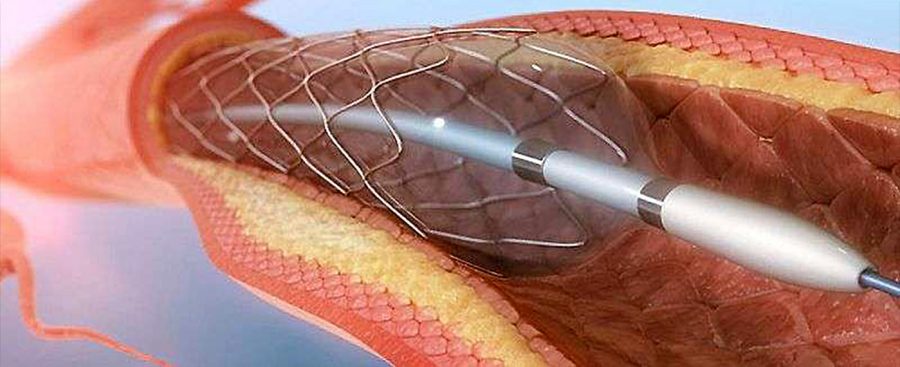

Αγγειοπλαστική με Μπαλόνι και Stent

Με τον όρο αγγειοπλαστική εννοούμε τη διαδικασία κατά την οποία με χρήση συρμάτων, καθετήρων, μπαλονιών μπορούμε να φτάσουμε σε μία βλάβη και να την διανοίξουμε. Η κλασική διαδικασία περιλαμβάνει διάνοιξη της βλάβης με χρήση μπαλονιού αγγειοπλαστικής και κατά περίπτωση χρήση stent. Τα μπαλόνια και τα stent υπάρχουν σε διάφορα μήκη και διαμέτρους ανάλογα το αγγείο που θέλουμε να διορθώσουμε.